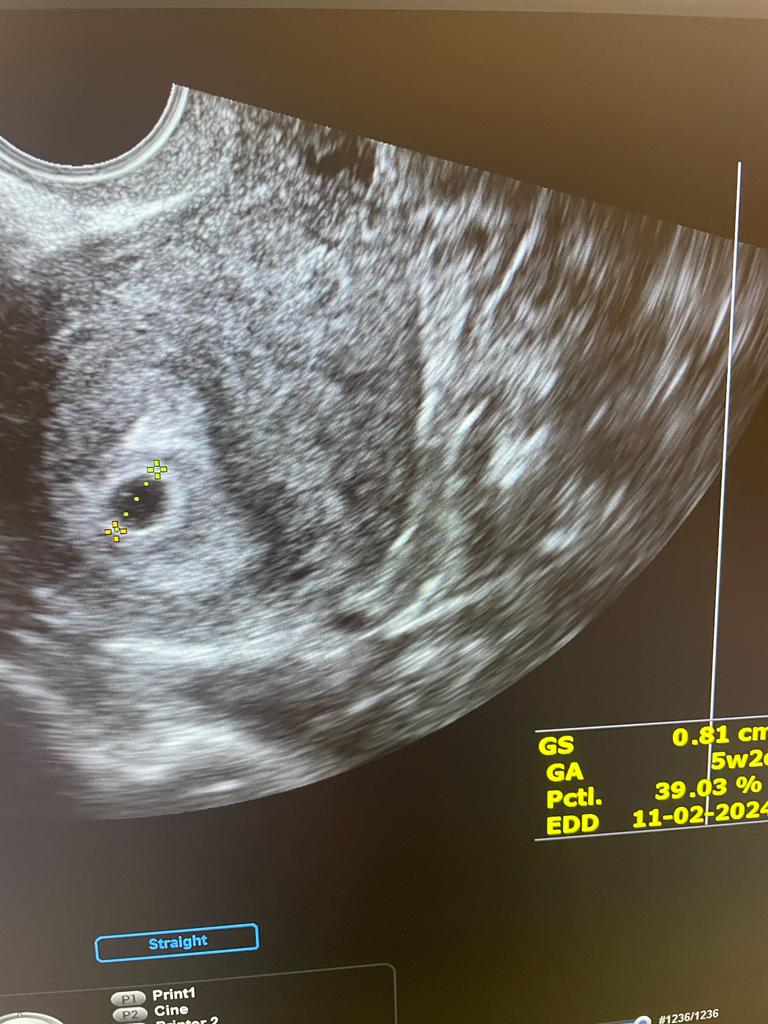

19.06 - Sterlicja pierwsze usg